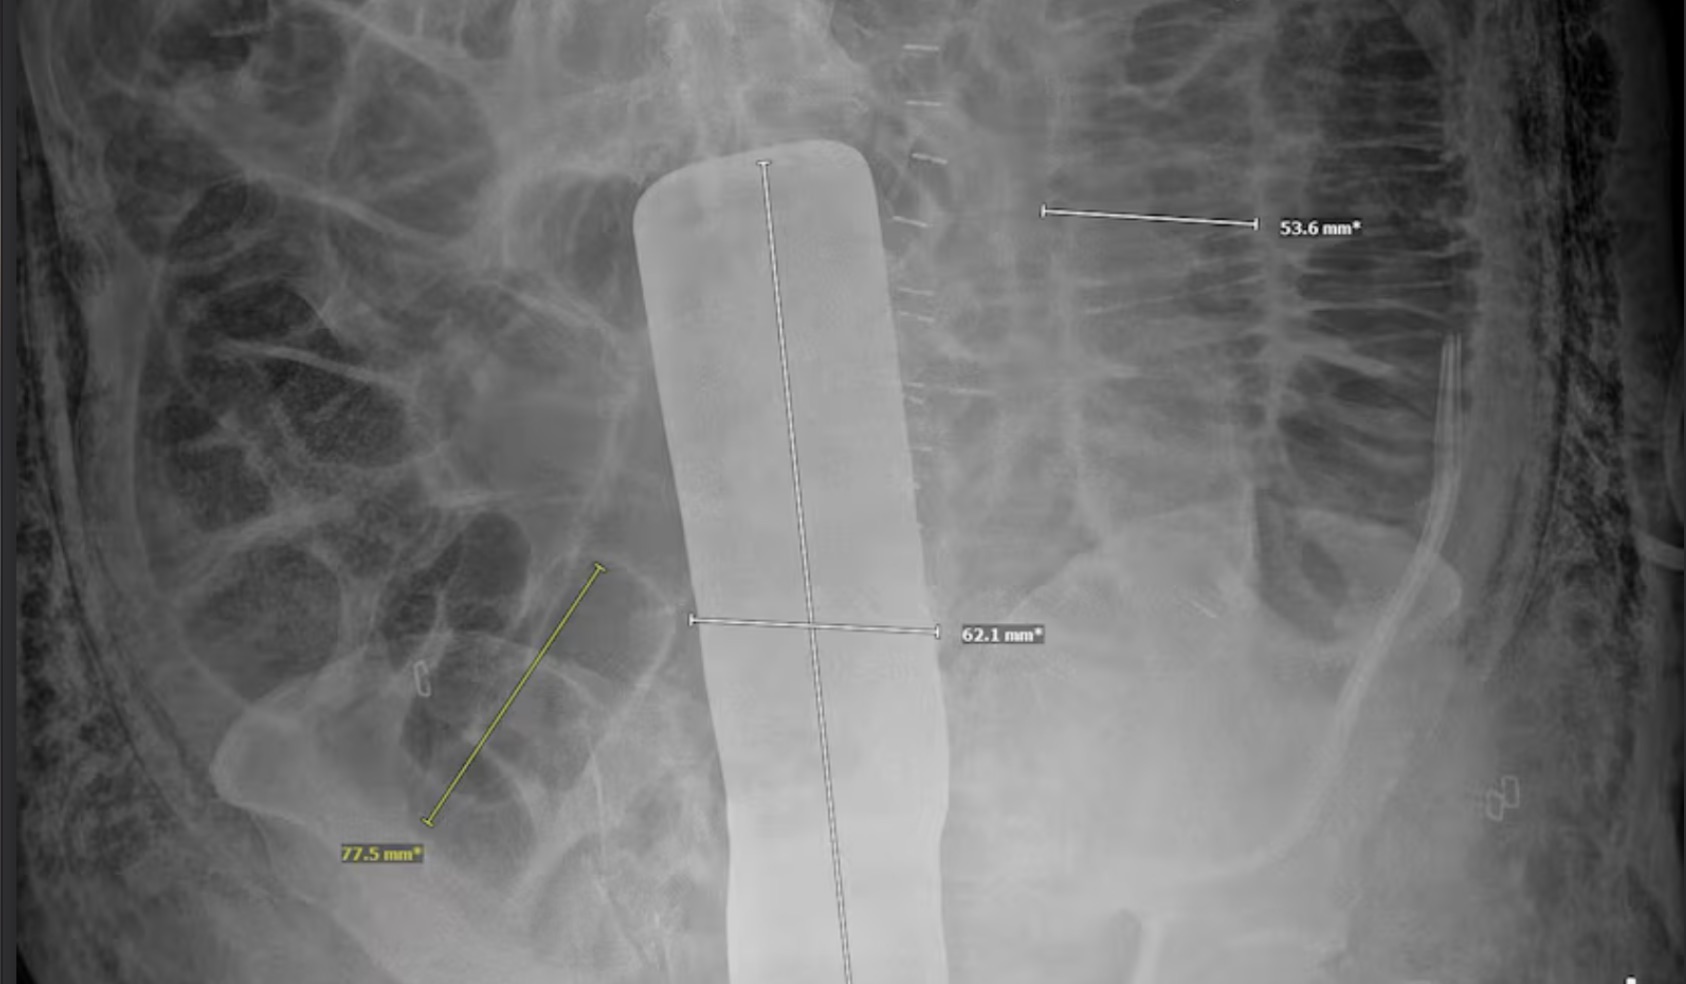

An X-ray ordered by his doctor revealed the instrument, which Nava’s attorney, Les Weisbrod, displayed during a Wednesday news conference. Four days after the tumor removal, Nava underwent a second operation to remove the tool.